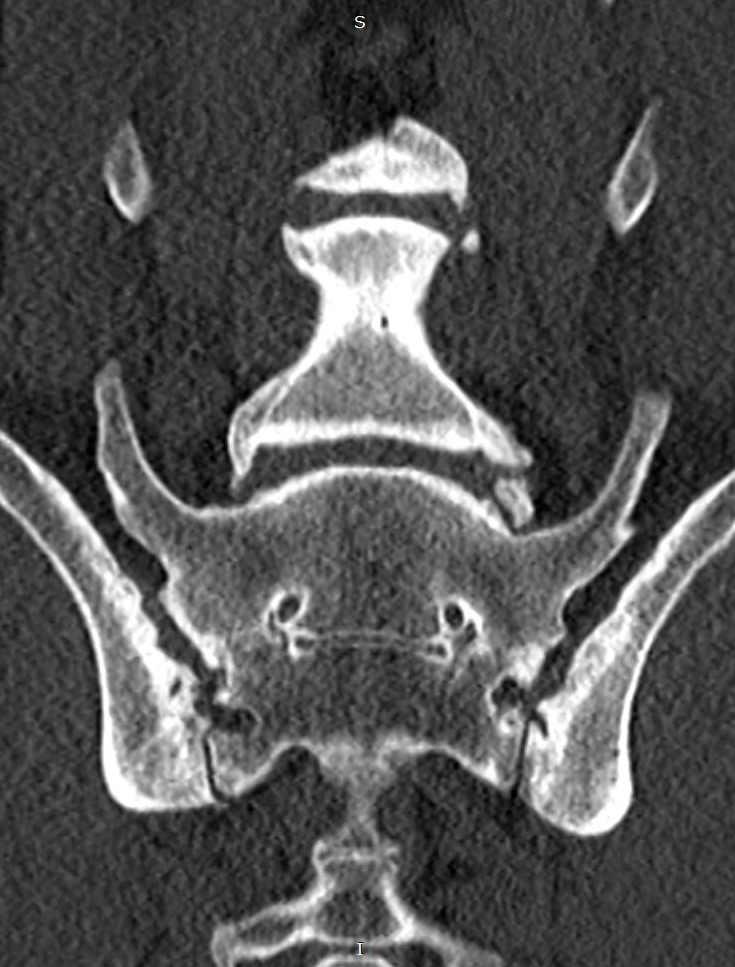

- Rekonstrukcós paraméterek

- A csontok megfelelő megjelenítéséhez bone-kerneles rekonstrukciós sorozat szükséges, hogy optimális kontraszt álljon rendelkezésre a csont és a környező lágyrészek között.

- A mátrixméret ideális esetben 512 × 512 legyen a megfelelő síkbeli felbontás biztosítása érdekében.

- A képek rekonstrukciója valódi axiális szeletekből, az eredeti CT-akvizíció alapján történjen.